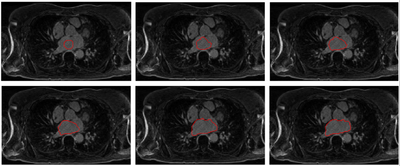

We propose an automatic approach for segmenting the left atrium from magnetic resonance imagery (MRI). The segmentation problem is formulated as a problem in variational region growing. In particular, the method starts locally by searching for a seed region of the left atrium from a given MR slice. A global constraint is imposed by applying a shape prior to the left atrium represented by Zernike moments. The overall growing process is guided by the robust statistics of intensities from the seed region along with the shape prior to capture the whole atrial region.

The proposed method consists of two key steps: (1) search for a seed region of the LA from an image slice in the axial view. (2) explore the LA region using a variational region-growing process. A shape prior is employed to drive the growing process towards atrium-like shapes.

Results

Image-LASegWithMomentsPrior.png